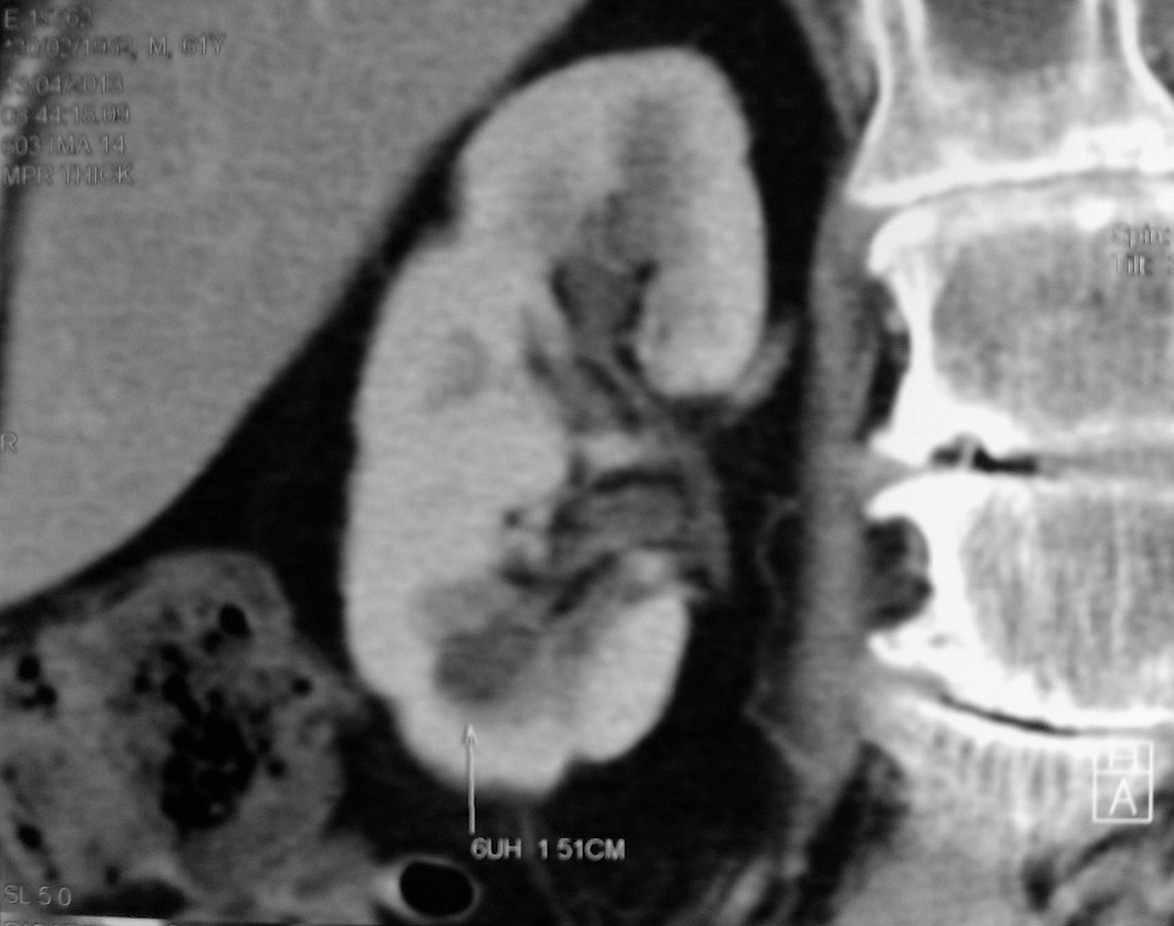

Case Discussion. A column of Bertin is the extension of renal cortical tissue which separates the pyramids, and as such are normal structures. They become of radiographic importance when they are unusually enlarged an may be mistaken for a renal mass ( renal pseudotumor ).. Hipertrofia de columna de Bertin: crecimiento anómalo de la cortical hacia el seno renal, que puede simular una masa sólida. Se produce entre el tercio medio y superior renal (fig. 1B).-Lobulación fetal: se diagnostica cuando la superficie del riñón presenta un marcado abombamiento, sin alteración en la anatomía renal corticomedular.-

La columna renal (o columna de Bertin, o columna de Bertin) es una extensión medular de la corteza renal entre las pirámides renales. Permite que la corteza esté mejor anclada. Una columna renal hipertrofiada (o pseudotumor renal) se puede diferenciar de un tumor renal real con la ayuda de una gammagrafía con DMSA. La exploración mostrará el área con actividad normal si se trata de un.. A: colocación de la sonda e imágenes ecográficas en los 2 cortes típicos de la exploración del aparato urinario. B: riñón en longitudinal con hipertrofia de columna de Bertin. C: riñón en transversal con quiste cortical. D y E: riñón con quistes sinusales en corte longitudinal y transversal.